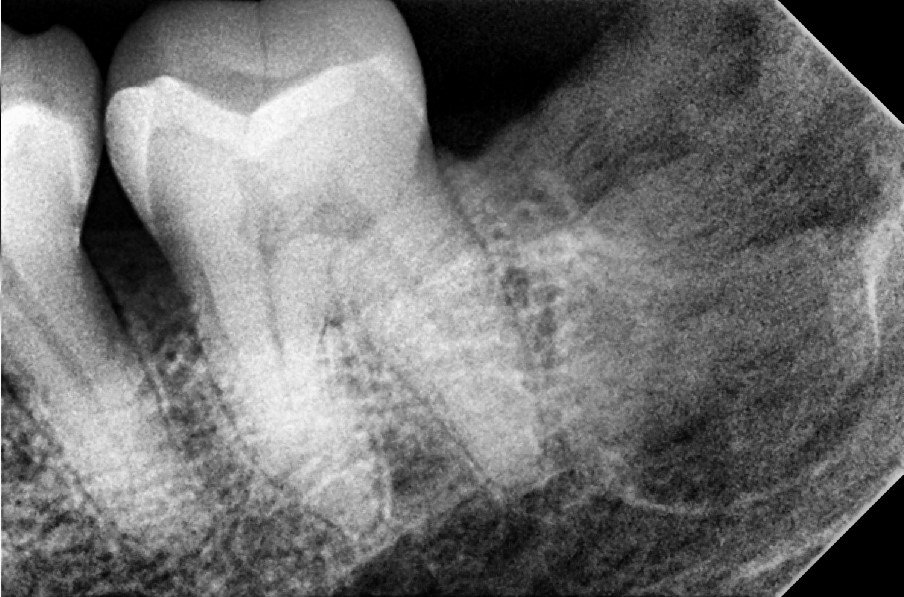

1. Comprehensive Consultation & Digital X-rays

We start with a thorough check-up using digital X-rays to assess the condition of the tooth and surrounding bone. This helps us plan the extraction precisely.